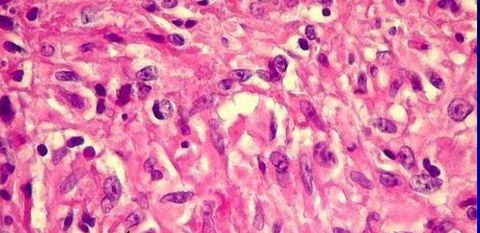

Diagnóstico, alterações e agente etiológico. LEISHMANIOSE DIFUSA Macrófagos com formas amastigotas, ausência de respostas inflamatórias. Leishmania amazonensis